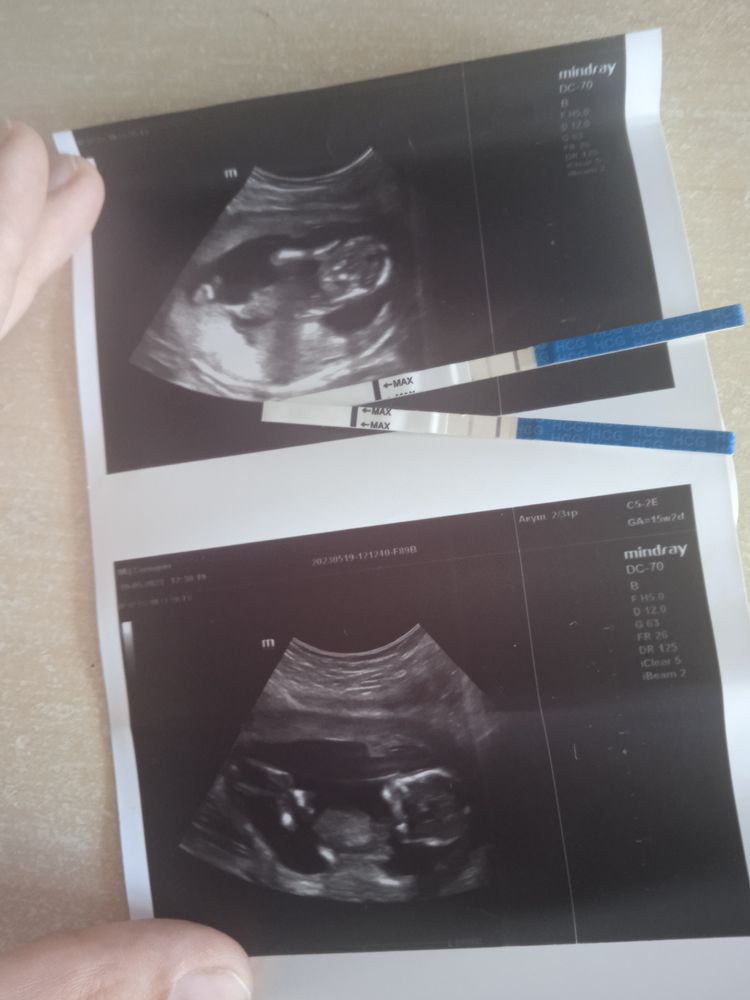

На узи нам не сказали, кто там, судя по многочисленным узи правильно ли я понимаю, что это и есть тот самый бугорок, который показывает девочку? 😁

На узи нам не сказали, кто там, судя по многочисленным узи правильно ли я понимаю, что это и есть тот самый бугорок, который показывает девочку? 😁